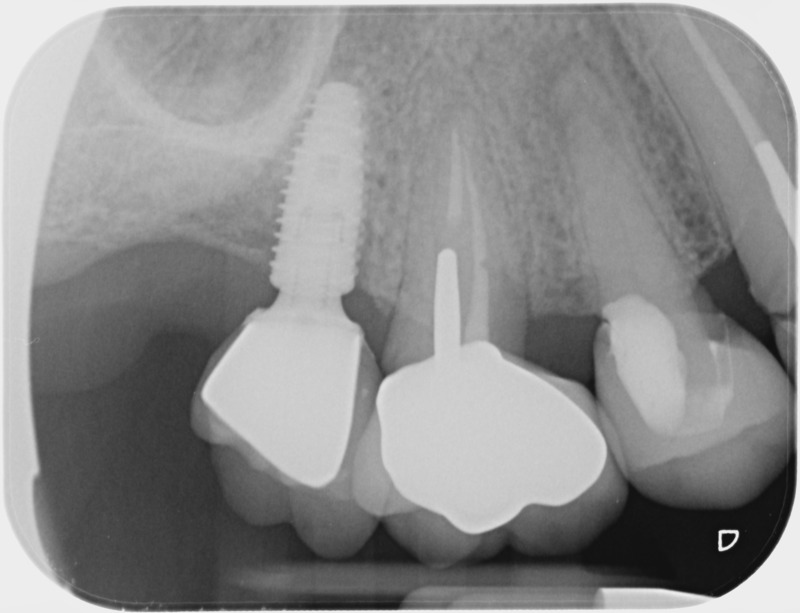

• Couronnes sur implants : Lorsqu’un implant est posé en remplacement des racines d’une dent, il est conçu pour recevoir d’abord un pilier vissé puis une couronne céramique. Le couple couronne - implant se substitue à la dent manquante pour en assurer les mêmes fonctions. Nous pouvons également adapter un bridge sur plusieurs implants dans le cas d’un édentement plus important.

Avant